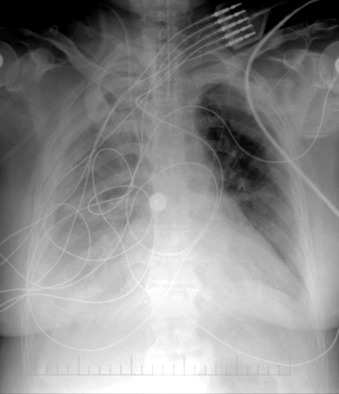

Chest radiography has a standard role to assess for the position of central venous lines and pulmonary artery catheters following their insertion.

Some postinsertion complications can be identified or excluded by chest radiography.

Determining malposition of catheters and tubes constitutes a forte of chest radiography and is mandatory following their insertion and repositioning.

Central Venous Lines ( Figs. 22-1 to 22-13 )

To avoid mechanical irritation (from the catheter tip) and chemical irritation (from infusate) of the right atrium, the catheter tip of a central venous line should be further than the junction of the internal jugular vein and subclavian veins (near the level of the first thoracic rib). In addition, the tip should not be further in than the junction of the superior vena cava and right atrium. Central venous catheters that are intended to record central venous pressure should lie distal to the last venous valves (in the subclavian and internal jugular veins, 2.5 cm proximal to the beginning of the brachiocephalic vein) and before the right atrium. The ideal position of the tip of a peripherally inserted central catheter (PICC) line is in the distal superior vena cava.